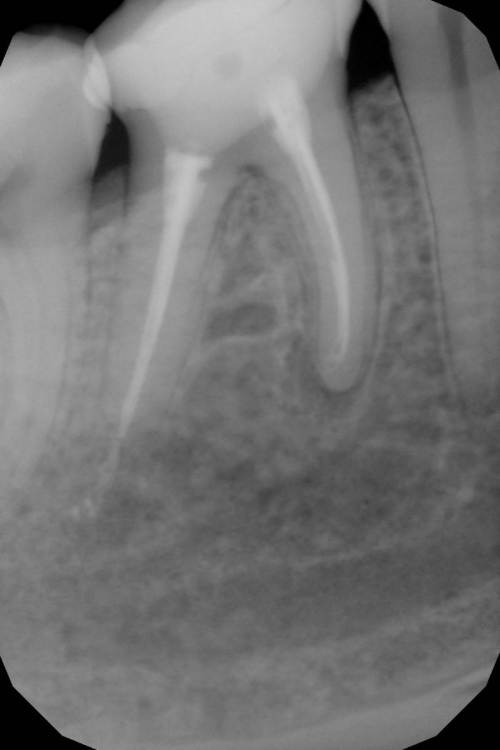

Перфорация. Симметрия каналов. Периодонтит

Как эта перфорация образовалась история умалчивает, оно и не важно, и так видно. Асимметричное расположение корневых каналов всегда наводит на мысли о неправильно раскрытом устье.

кальцием пафнуло дистально